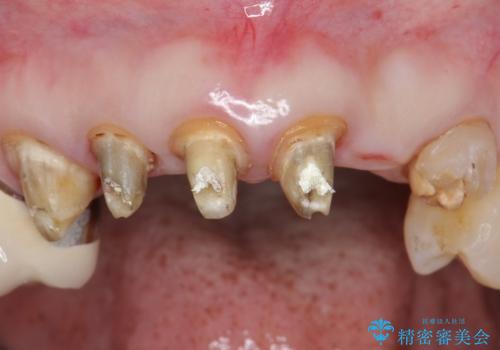

上の前歯6本はメタルボンドクラウン(内側が金属の被せ物)で補綴されており、顕著な歯肉退縮を認めました。

被せ物を除去したところ根管治療後の処置が不十分であったため、ファイバーコア(金属を用いない強くてしなやか材質の土台)を植立したのち、ジルコニアセラミッククラウンによる治療を行いました。